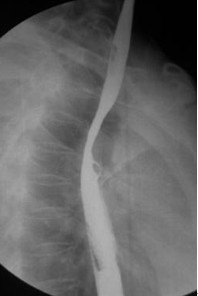

女,51歲,以“進(jìn)行性吞咽困難1年”為主訴于2007年2月19日入院。鋇餐造影、胃鏡示食管上段占位性病變,確診為食道鱗癌(圖1),拒絕手術(shù),行放療+今又生治療。食道鏡下瘤內(nèi)注射今又生,1×1012VP/次/周×6,放療在今又生注射3 d后開始,采用常規(guī)分割三野等中心照射,劑量65cGY。治療結(jié)束后4周,食管X線、胸部CT顯示腫瘤完全消退(圖4-5)。

治療前

放療40GY+今又生4支后

放療65GY +今又生6支后

放療結(jié)束4周后